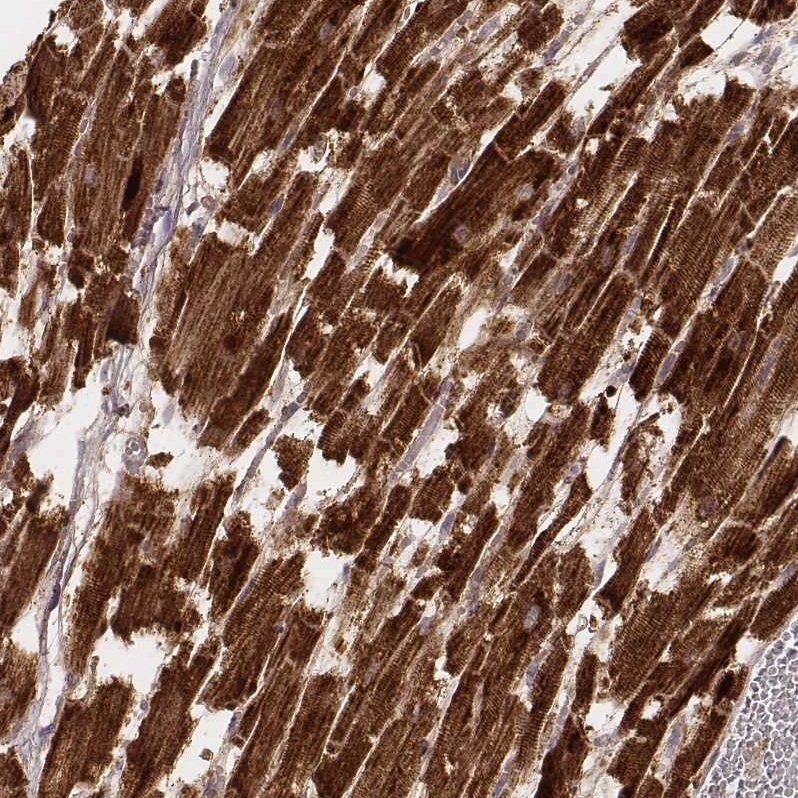

Immunohistochemistry analysis in human heart muscle and liver tissues using AMAb91006 antibody. Corresponding CS RNA-seq data are presented for the same tissues.